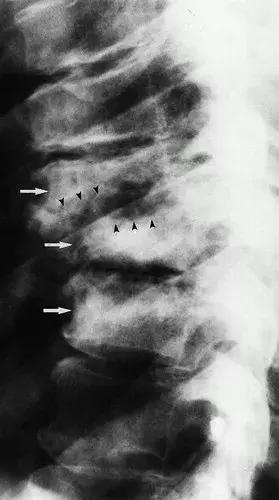

图6:45岁男性患有神经性脊柱,C6平面下的四肢截瘫,合并新的长束征( long-tract signs)(a)侧位X线片显示T7至T9椎体的破坏性,伴有半脱位,终板破坏(箭头),硬化(箭头)和骨赘形成。 (b)矢状T2加权自旋回波MR图像(4,000/96)显示脊髓硬膜外椎体的压迫(箭头); 然而,没有椎旁肿块或硬膜外脓肿。